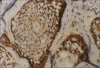

Materials and methods: Ameloblastoma cases consisted of follicular, plexiform, and unicystic subtypes. The positive staining was assessed based on intensity of staining, localization of staining, and in different cell types in both the tumors. Two cases of follicular ameloblastoma and one case of plexiform ameloblastoma showed intense staining, but the predominant staining intensity was overall mild in both ameloblastoma and adenomatoid odontogenic tumors. The immunoreactivity was found both in nucleus and cytoplasm in ameloblastoma and only nuclear in adenomatoid odontogenic tumors. The peripheral columnar and central stellate reticulum-like cells of ameloblastoma showed immunoreactivity with squamous and granular cells being negative. In adenomatoid odontogenic tumors, the whorls showed predominant localization of staining. Statistical comparison with a Mann-Whitney U-test showed no significant difference in staining intensities between different histologic subtypes of ameloblastomas and also between ameloblastoma and adenomatoid odontogenic tumors (P>0.005).